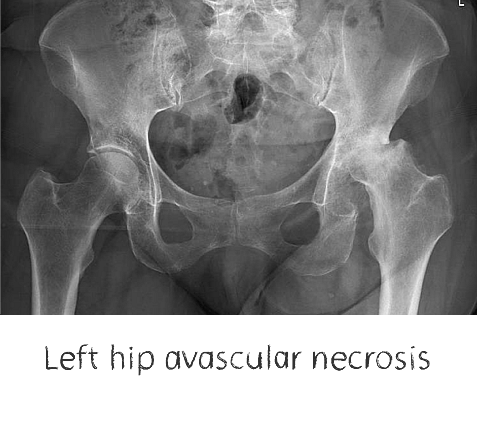

Plain film x-rays are taken to assess the joint

These are usually taken prior to your appointment. These help to confirm the diagnosis, assess the wear pattern and look for particular deformities. They can show old metalware and its position in the bone.